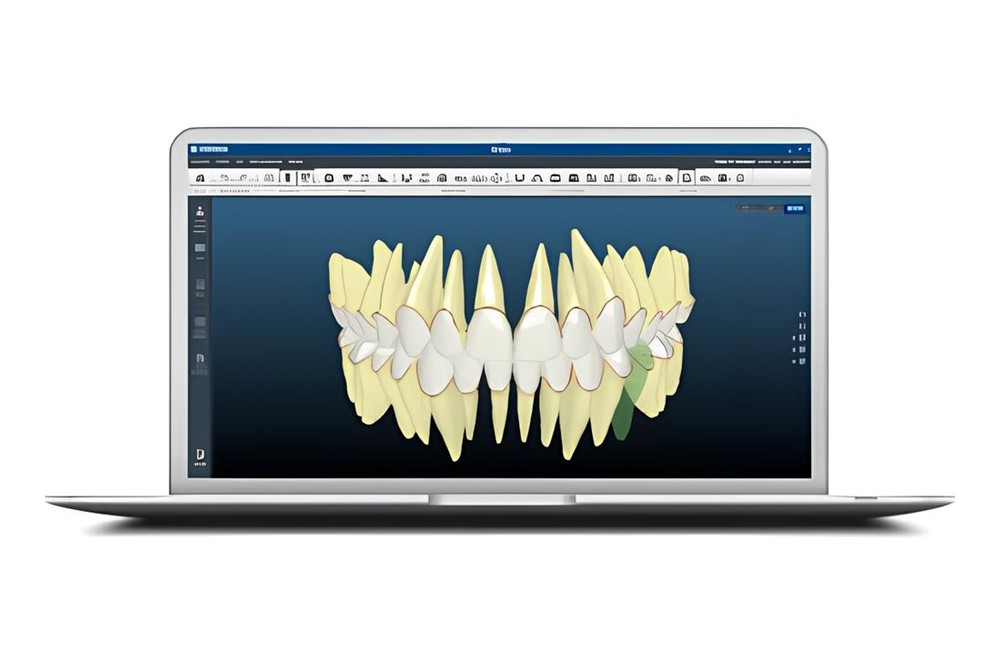

当院では、矯正治療における診断と治療計画の精度向上のため、完全デジタル化を推進しています。

歯列だけでなく顔全体のバランスまで考慮するために、3D顔面スキャンシステムを導入しています。

患者さまのお顔全体を非接触で数秒スキャンするだけで、歯並びと顔立ちとの調和を立体的に可視化することが可能です。

こうした情報は、治療前後の仕上がりイメージの共有や、違和感の少ない自然な仕上がりの設計に活かされています。

また、従来のような粘土の型取りを必要としない口腔内スキャナーを用いた3Dデータ取得もあわせて行うことで、

診断から設計・作製に至るまでの工程を一貫してデジタルで構築しています。

当院では、インビザラインで知られるアライン・テクノロジー社が開発した口腔内スキャナー「iTero Lumina(アイテロ ルミナ)」を導入しています。

このスキャナーは、今までの機種と比べてスキャン精度やスピードが向上しており、歯や歯ぐきの状態をより精度良くに、短時間で読み取ることができます。

取得したデータはその場で3D表示できるため、治療内容を視覚的にわかりやすくご説明できるのも特徴です。

コンピューターデジタル設計を基に、治療前に歯の動きを3Dシミュレーションで確認できるため、治療の全体像を事前に把握したうえで進めることができます。